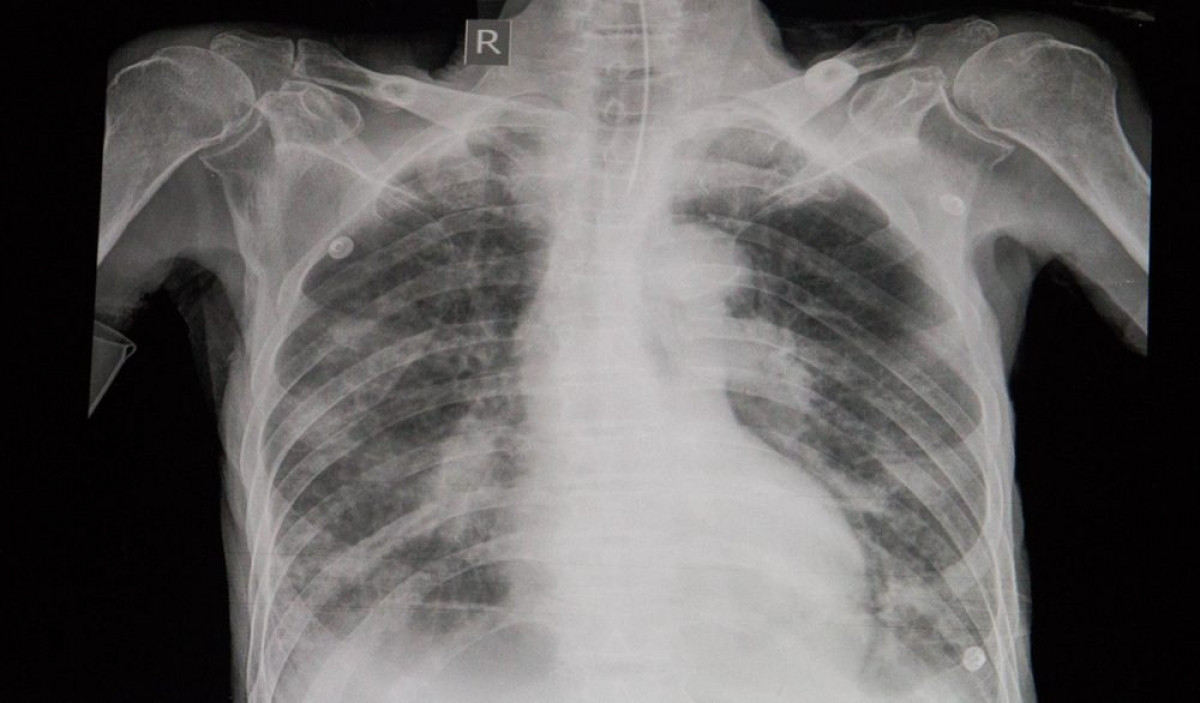

Khó thở: Khó thở hoặc thở gấp mà không phải do nghẹt mũi là những dấu hiệu cho thấy bạn đã gặp phải biến chứng của bệnh cúm. Các dạng nhiễm khuẩn thứ phát như viêm phổi có thể khiến bạn gặp phải tình trạng này.